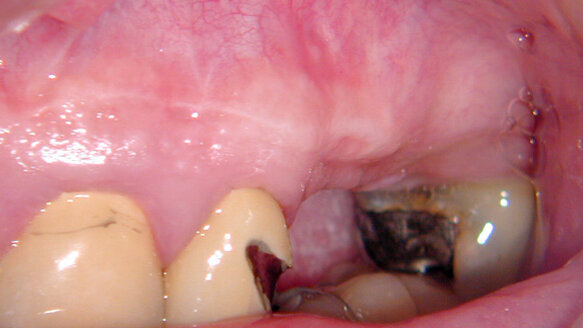

In other words, it is easier to guide a TPN to the desired point of exit in the attached tissue than it is a RCN. They just seem to cooperate more when suturing this type of flap! One of the nicest things about using this flap design is the ability to easily see the healing taking place (Figs. 2–6)